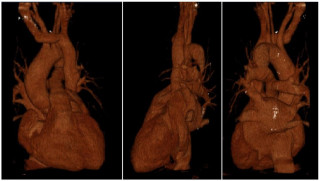

An 82-year-old otherwise healthy man was referred for evaluation of an incidentally detected left adrenal mass. The patient was asymptomatic with no clinical signs of catecholamine excess, hypercortisolism, hyperaldosteronism or B-symptoms. Initial CT scan revealed a 44 × 42 mm lesion, which increased to 50 × 46 mm within three months and suspicious washout characteristics (Figure 1). Endocrinological work-up showed a pathological dexamethasone inhibition test, while metanephrines and aldosterone testing was normal. Tumor markers (AFP, β-HCG) were unremarkable. A hormonally active adrenal adenoma with autonomous cortisol production was suspected.

After discussion at the interdisciplinary tumor board, robotic-assisted adrenalectomy was performed (Figure 2). Complete resection was achieved without complications, the patient was discharged on the third postoperative day.

Histopathological examination showed a Sertoli cell tumor with complete excision and no evidence of local infiltration or malignancy (Figure 3).

Immunohistochemistry showed positivity for CD56, CD99, synaptophysin and partial positivity for SF1, calretinin and inhibin. Chromogranin A and MART1 were negative. Molecular analysis revealed no FOXL2 or DICER1 mutations. Postoperatively, hydrocortisone substitution was initiated due to submaximal cortisol response in ACTH stimulation testing. At six-month follow-up, CT imaging showed no recurrence or metastases and tumor markers remained normal.